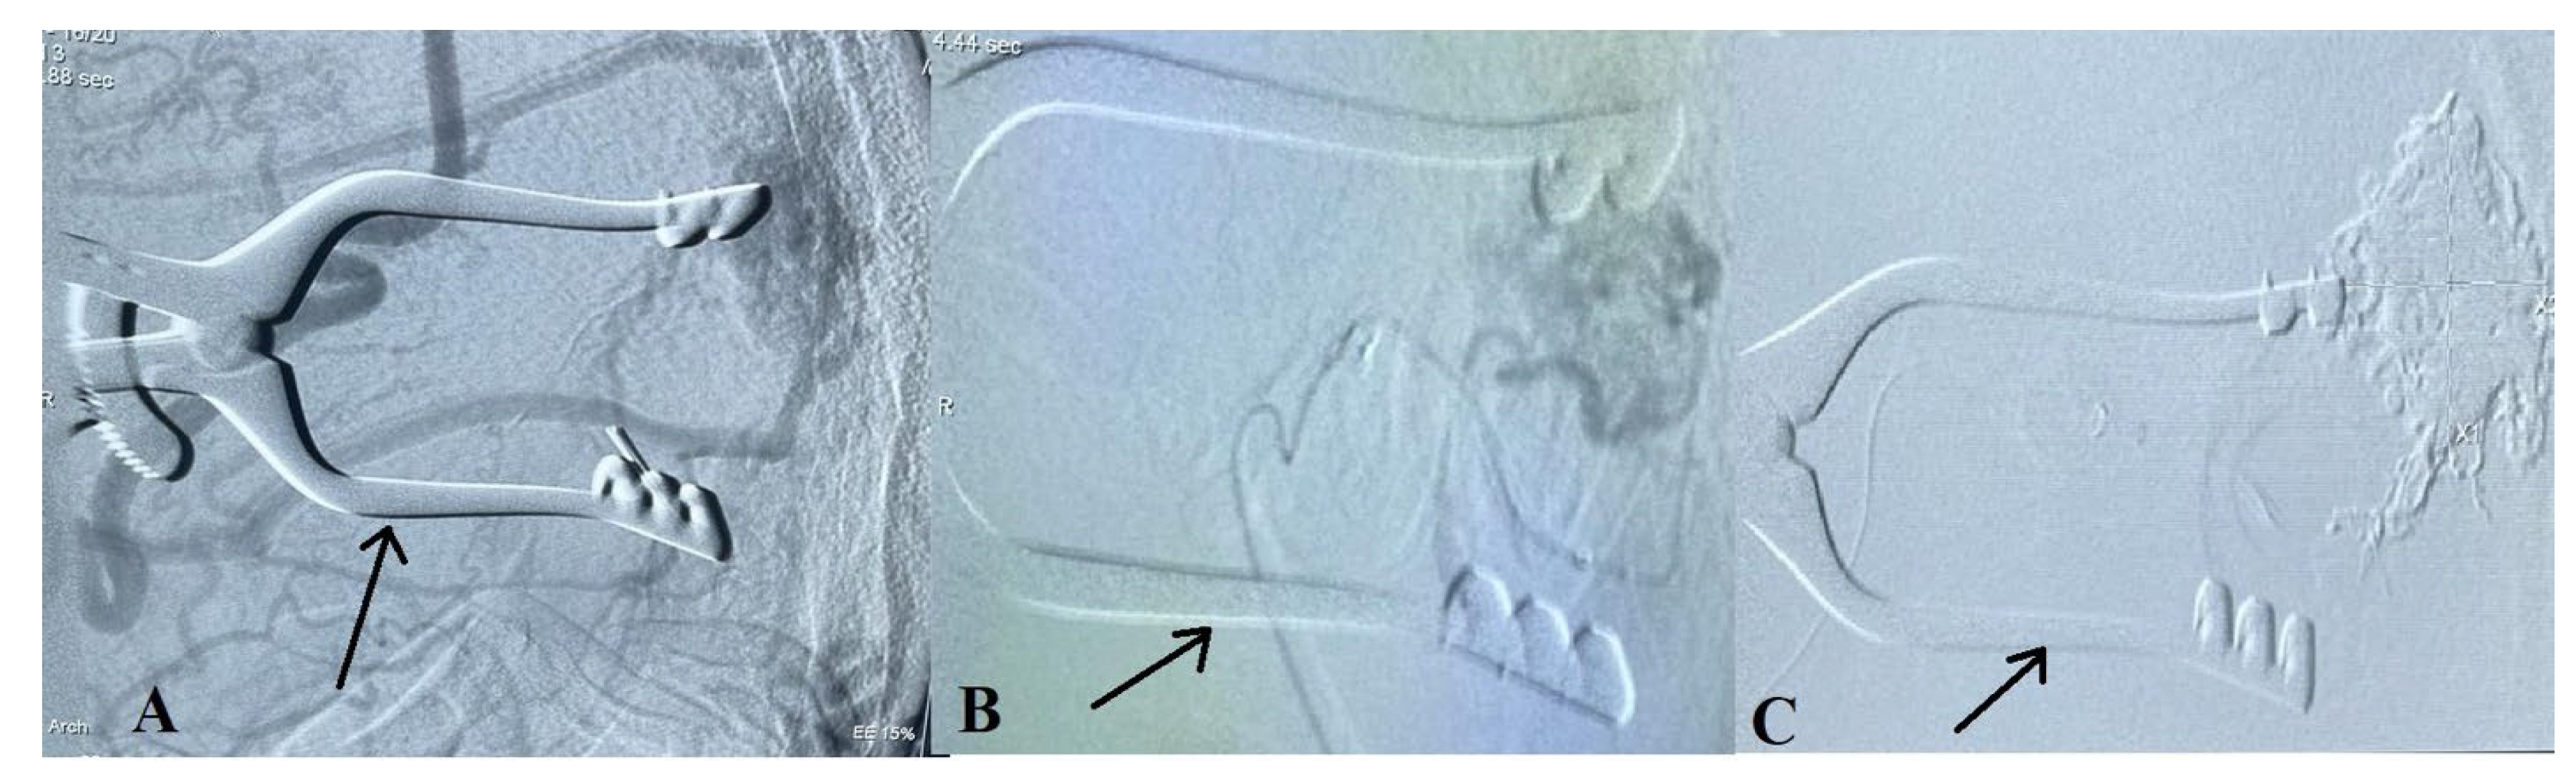

2.2. Treatment